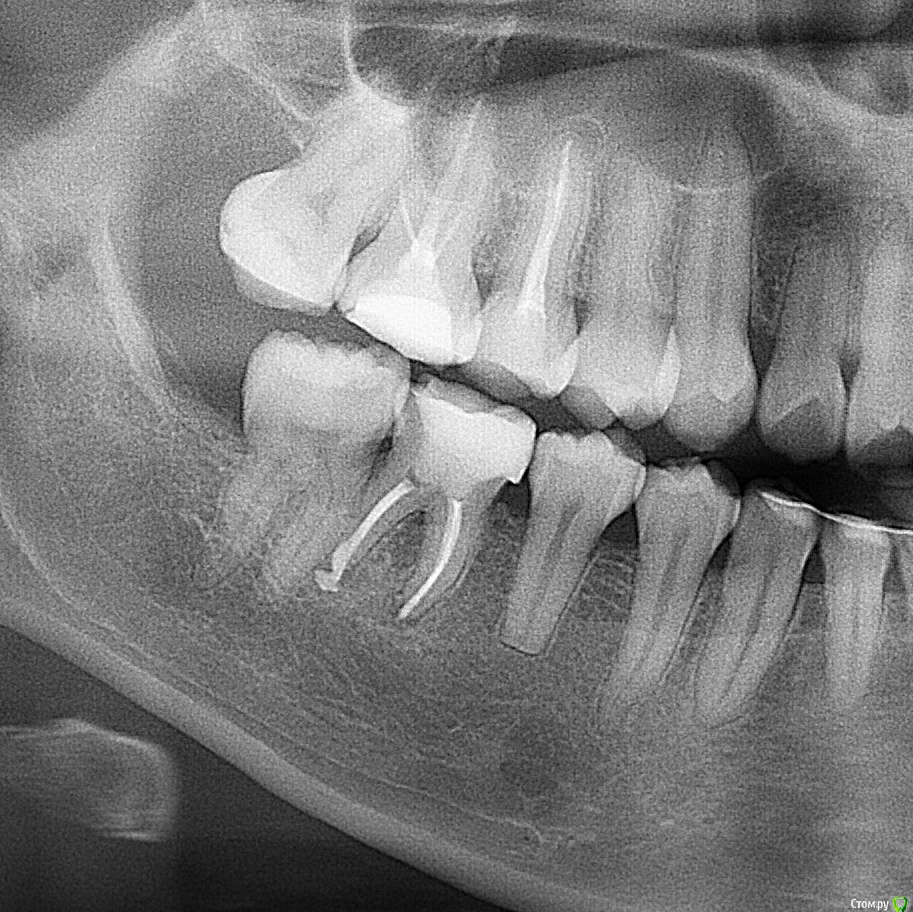

Анастасия2706 Опубликовано 20 мая, 2018 Поделиться Опубликовано 20 мая, 2018 (изменено) Здравствуйте! 2 месяца назад на задней стенке шестёрки появилась дырочка, пломбу на зуб ставили лет 5 назад, нерв удален. Зуб не беспокоил. К стоматологу обратилась только сейчас.Он заключил, что нужно ставить коронку. Ортопед заметил потемнение между корнями, сказал, что установка коронки может усугубить процесс, но всё-таки было решено ставить коронку с вкладкой. 1. Можно ли это делать в таком случае? Меня этот зуб давно не беспокоил, но последние дни начал болеть. Точнее, болит не зуб, а десна рядом с дырочкой при нажатии на неё.2. Может ли быть причиной то, что обострилось воспаление? Или скорее то, что в отверстие постоянно попадает пища и я беспокою его зубочисткой? 3. Может ли это воспаление рассосаться после установки коронки? Прочитала на форуме, у одной девушки после пломбирования каналов так и произошло. Посоветуйте, пожалуйста!На снимке нижний зуб второй слева. Изменено 20 мая, 2018 пользователем Анастасия2706 Ссылка на комментарий

red_butler Опубликовано 20 мая, 2018 Поделиться Опубликовано 20 мая, 2018 Воспаление десны устраняется протезированием, всё верно. Зуб ещё послужит.только если не подтвердится фуркационный дефект, который видно на снимке... Ссылка на комментарий

Дмитрий Л. Опубликовано 22 мая, 2018 Поделиться Опубликовано 22 мая, 2018 У вас кариес 46 по задней стенке. Следствие - скопление налёта и острые грани, приводящие к травме десны. Возможно что есть кариес 47 по передней стенке, что также играет роль. Протезирование или пломбирование решает вопрос. Разрежение между корнями нуждается в очной консультации, это может быть вариантом нормы или же дополнительной причиной воспаления. Врач это увидит. Зуб достаточно проблемный но при отсутствии другой симптоматики можно протезировать, на несколько лет хватит. Но вы должны взять риски на себя. Удаление одного из корней и любые другие подобные паллиативные методы бессмысленны. По показаниям можно сделать кюретаж, почистить всё между корнями. Это решает ваш врач. Ссылка на комментарий